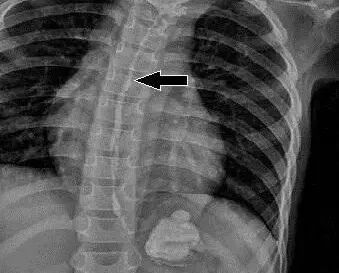

纽扣电池福州儿童医院耳鼻咽喉科曾收治了两名误吞纽扣电池的患儿。其中一名患儿,性别女,1岁,误吞纽扣电池5天;另一名患儿2岁,性别男,误吞纽扣电池5小时。经检查,两名患儿的食道黏膜均遭腐蚀!并且,电池呈黑色!